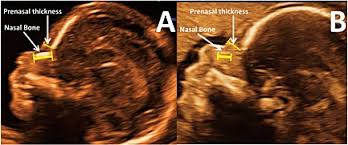

Examples Of Nasal Bone Length And Prenasal Thickness Measurements Download Scientific Diagram